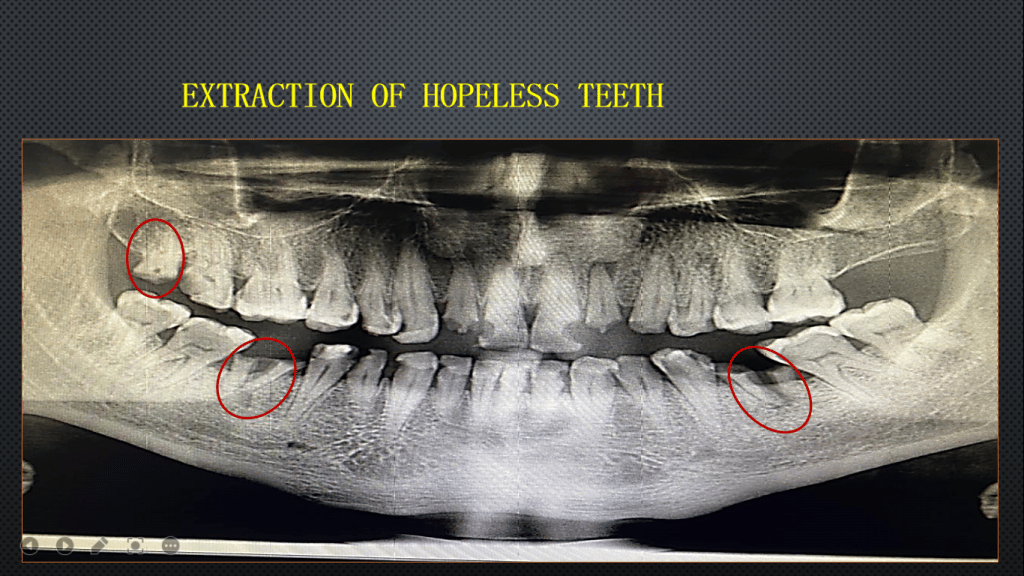

1.Extraction of hopeless teeth.

We extracted hopeless teeth

Tooth number #36

Tooth number #46

Tooth number #18